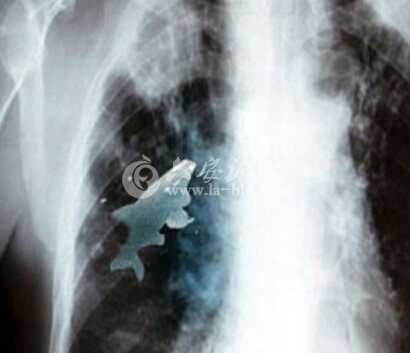

2012年5月,印度一名12岁男孩在一条河中玩耍时呛水,不慎将一条小金鱼吸入肺中。医生迅速为他进行手术,取出了这条“肇事小鱼”。

医生表示,在他们用支气管镜检查时发现,巴瑞拉肺中的小鱼依然活着。